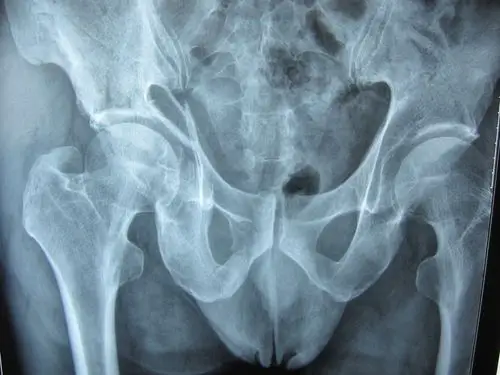

髋臼骨折,是否要手术治疗?